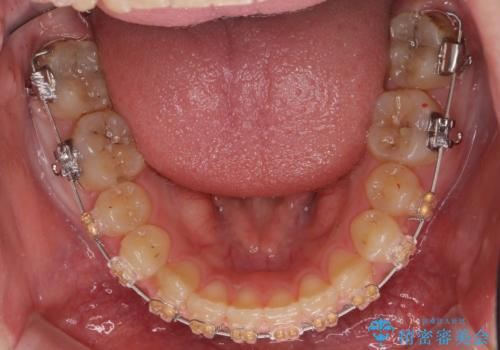

- 矯正装置

- 審美装置

- 上の小臼歯を2本抜歯して矯正を行いました。

一般的には、抜歯を行うと前歯はより内側に倒れこむため、初めから内側に倒れ込んでいると矯正の難易度は上がります。

今回は上の前歯が内側に傾いている症状があり(Angle Ⅱ級2類)、その修正に時間がかかっています。